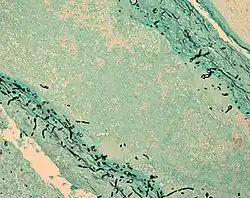

Fungus (black) in brain tissue